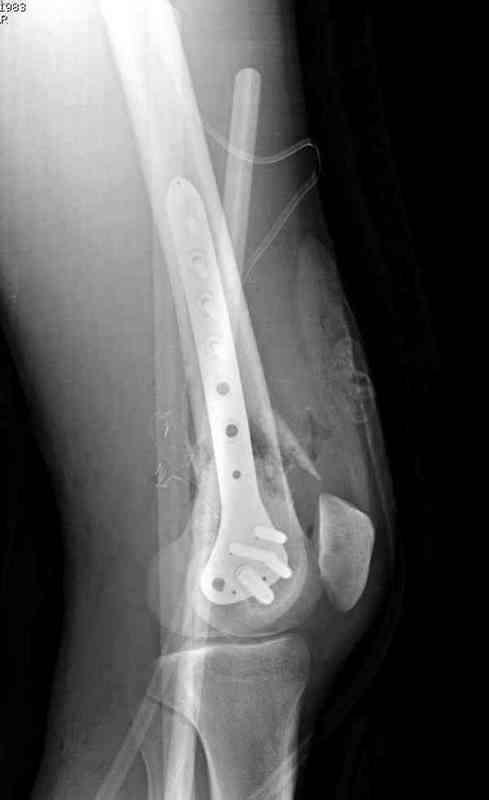

На третий день после Irrigation & Debridment закрыли все раны за исключением компартментальной раны из-за отека, медиально в дефект кости установили Putty Grafton Bone Substitute. На компартментальную рану вакуум и мероприятия по сближению краев раны резиновой стяжкой.

На 9й день с момента травмы ушили рану без натяжения. Больной получает реабилитацию, движения коленного сустава с помощи CPM-continuous passive motion machine. Сегодня выписан.